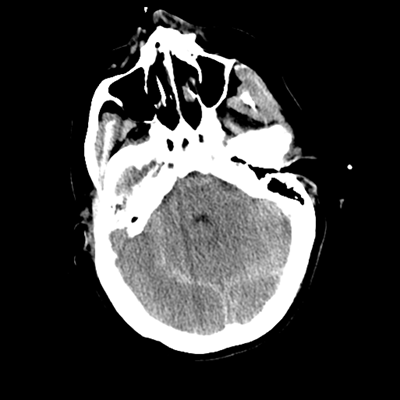

The patient goes down to CT. The following images are obtained. The subdural fluid collection is stable, as is the ventricular caliber.

NCHCT

Starting with the non-contrast head CT, we can appreciate that there's actually not much residual subarachnoid blood at all; it's essentially all resorbed already (and cleared through the EVD). The ventricular caliber is stable. With the CTA head (for convenience's sake, the MIPs were shown), it's subtle, but we can see that the PCAs on each side are not as smooth and regular. The right MCA, starting at the bifurcation, also becomes narrower. This is [radiographic] vasospasm. Now, looking at the CT perfusion-- specifically, the Tmax (MTT) map that were selected-- there's clearly some abnormality within the bilateral cerebellar hemispheres and occipital lobes. Not a lot, but it's there. Delving further into this map, we can appreciate that the areas of abnormality are mainly green, signifying that these areas have Tmax > 6 seconds. This is the threshold that is specific, not sensitive, for vasospasm.